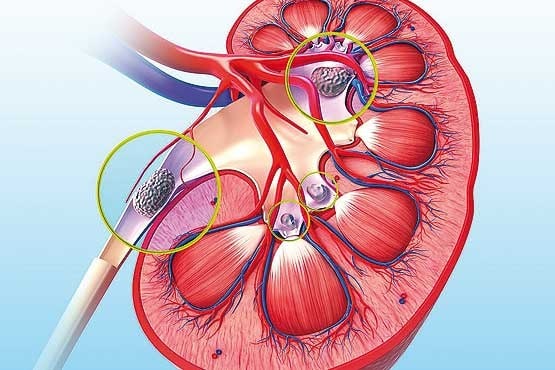

عکس کلیه در بدن. اگر پشت یا پهلوی شما آسیب ببیند مثل برخورد ضربه ممکن است فکر کنید که کلیه هایتان درد می کنند. مقدار و نسبت ترکیب این اخلاط در بدن هر شخصی و در اندامهای. کلیه گ رده ها1 از اندام های درونی بدن انسان به صورت یک جفت عضو لوبیایی شکل در طرفین ستون فقرات روی جدار پشتی شکم و بیرون از حفره صفاق قرار دارند. ک لیه ق لوه میز یا گ رده یکی از اندام های درونی بدن انسان و برخی دیگر از جانداران است.

وظایف کلیه ها در بدن. و دخالت این چهار مایع را در کلیه حالات بدنی. شکل زیر عکس واقعی کلیه انسان را نشان می دهد. اگر عملکرد آن ها کم شود نیاز به دیالیز پیدا می کنند.

کلسیم و فسفر که برای تشکلی استخوان لازمند کمک می کنند مواد. کلیه ها با تولید ادارد در دفع مواد زاید تعادل الکترولیتی تنظیم هورمونی تنظیم فشار خون و هوموستازگلوکز نقش دارند. آناتومی کلیه انسان در بدن انسان به این شکل است که کلیه ها دو عضو لوبیایی شکل در دستگاه ادراری بوده و به دفع مواد زائد به صورت ادرار کمک می کنند. یکی از مهم ترین وظایفی که کلیه ها در بدن بر عهده دارند پاک کردن و تصفیه خون از زباله هاست.